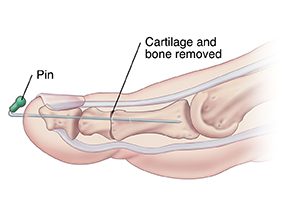

Fusion

First, the cartilage and some bone on both sides of the joint are removed. Then, the toe is straightened, and the 2 bones are held together, often with a pin. The pin is removed after several weeks. Once your foot heals, the toe will be less flexible, but more stable.

| Fusion. |